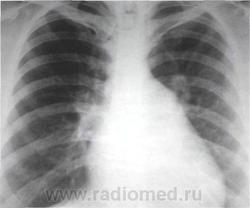

Изменения рентгенографической конфигурации сердца в переднезадней проекции обусловлены, прежде всего, сглаживанием талии из-за увеличения полости левого предсердия и его ушка с расширением третьей дуги по левому контуру сердечной тени

Рентгенограмма сердца в переднезадней проекции больного с митральным стенозом. Митральная конфигурация сердца

Увеличение размеров сердечной тени при митральном стенозе не столь велико, как при митральной недостаточности. В большинстве случаев поперечник сердца увеличивается равномерно в обе стороны. Степень выбухания и протяженность третьей дуги соответствуют размерам ушка левого предсердия. За - падение третьей дуги отмечается у больных, перенесших закрытую митральную комиссуротомию, что соответствует маленькому, сморщенному или перевязанному, а иногда ротированному кзади ушку левого предсердия. При западении третьей дуги можно

Предполагать тромбоз ушка левого предсердия, которое обычно сморщивается. Часто при увеличении левого предсердия выявляется добавочная дуга на фоне верхней половины сердечной тени близ правого контура или она непосредственно участвует в образовании правого контура. Добавочная дуга обрисовывает нижний правый контур левого предсердия, что на фоне тени сердца выглядит как тень двойной интенсивности из-за значительного увеличения переднезаднего размера левого предсердия. Особенностью сердечной тени у больных митральным стенозом в переднезадней проекции является хорошая дифференциация дуг левого контура из-за подчеркнутой выпуклости ушка левого предсердия и легочной артерии.

Вследствие увеличения третьей дуги размеры дуги левого желудочка могут быть относительно уменьшены. Иногда верхушка сердца слегка приподнимается над диафрагмой из-за оттеснения ее влево и вверх правым желудочком, размеры которого при высокой степени легочной гипертензии преобладают над размерами левого желудочка .